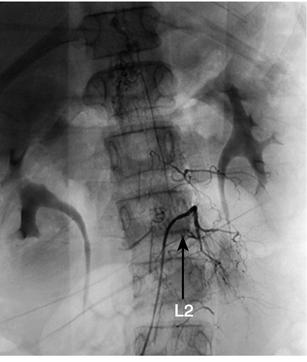

诊疗经过:入院后行腰椎穿刺术,连续留取3管脑脊液,均为淡红色血性脑脊液,脑脊液化验结果除外中枢神经系统感染。2010年10月28日晚19时40分患儿站立中诉腿疼,平卧后再次出现抽搐,表现为口吐白沫、双手握拳、双上肢屈曲、颈部强直,并有意识障碍。予吸氧、镇静止惊、改善脑水肿等对症治疗,仍反复抽搐多次。急诊行颅脑CT检查,示脑室及蛛网膜下腔少量出血(图3)。遂由儿内科转神经外科治疗。转科后行全脑全脊髓血管造影提示:T11~L2脊髓血管畸形(图4)。遂于2010年11月10日在全麻下行T11~L2脊髓畸形血管团切除+椎板扩大成形+硬膜修补术。术后给予脱水、抗炎、止血、补液、支持、神经营养、激素等治疗后患者意识逐渐转清,未再抽搐,病情稳定出院。

图4 全脑全脊髓血管造影(2010年10月29日)提示:T11~L2硬脊膜动静脉瘘(箭头)

本例入院前反复抽搐起病,考虑每次出血量不多,随着出血吸收,症状缓解。入院后根据患儿脑膜刺激征、血性脑脊液及颅脑CT检查不能除外蛛网膜下腔出血。行全脑血管造影术未发现颅内血管畸形,继续向下行脊髓血管造影证实为胸腰段脊髓血管畸形致脊髓蛛网膜下腔出血并反流入脑室系统和蛛网膜下腔导致抽搐和意识障碍。

根据血管造影的表现,通常将脊髓血管畸形分为4型:髓内动静脉畸形、膜内髓周动静脉瘘、硬脊膜动静脉瘘和混合型动静脉畸形[3]。临床上以硬脊膜动静脉瘘最常见,是指在神经孔处硬脊膜上多发的动静脉瘘,动脉供血主要来源于节段性动脉的硬膜分支,静脉回流至脊髓的冠状静脉丛,静脉引流主要位于脊髓背侧,可贯穿脊髓全长。发病机制主要为静脉高压引起脊髓及神经根淤血、水肿。脊髓盗血、血栓形成、畸形血管局部占位、静脉高压以及出血均可有如下表现:后背及神经根痛、截瘫、横贯性感觉障碍、括约肌功能及性功能障碍,而蛛网膜下腔出血、腹壁牵涉痛等少见[4]。本例患儿脊髓血管造影表现符合硬脊膜动静脉瘘,之所以无截瘫等表现,可能与出血量少、畸形血管团尚未对脊髓造成明显压迫有关。